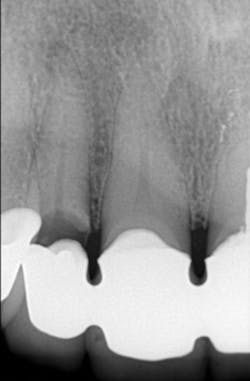

Moderate-to-severe pain (figures 4-8)

Figure 4: Patient with splinted anterior crowns and large carious lesion on lateral incisor had moderate constant pain

Figure 5: Patient had moderate postoperative pain after tooth preparation appointment.

Figure 6: Patient had almost no postoperative pain after tooth preparation appointment. Both patients in Figures 5 and 6 had same apparent trauma during tooth preparation, but they reported very dissimilar postoperative pain.